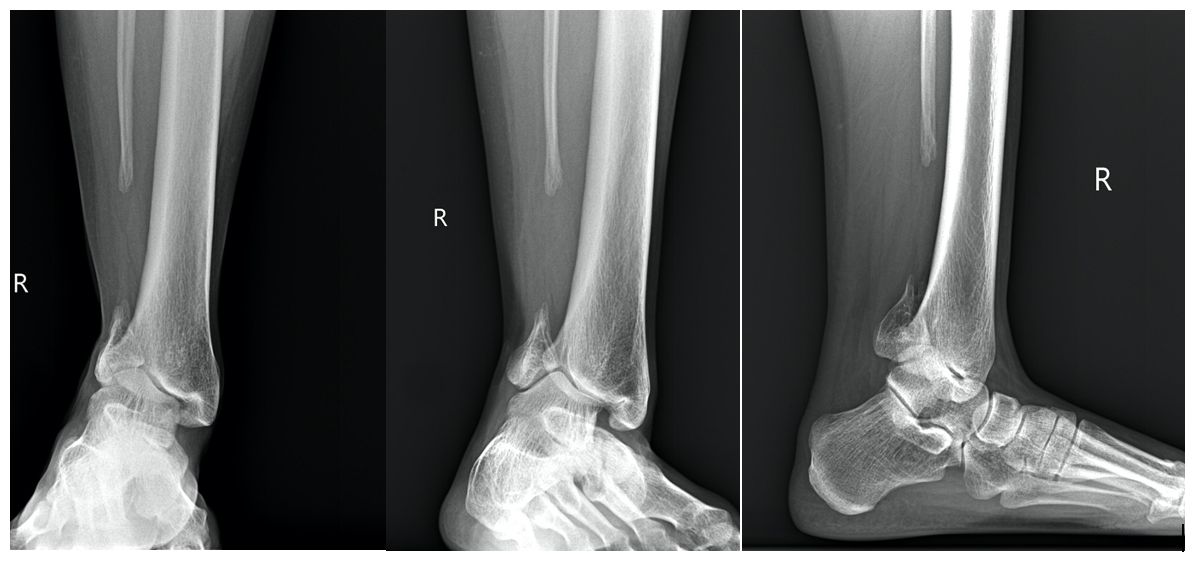

Radiographic evaluation of the right ankle revealed a significant fibular bone defect with bony consolidation of the free ends. A valgus malalignment is evident at the ankle joint. A weight-bearing AP radiographic view shows narrowing of the ankle joint space and overlapping of the distal fibular segment with the tibia. The lateral view of this radiograph reveals an anterior overlap of the distal tibia and the talus. There is a visible decrease in bone mass of the proximal fibular segment and an increase in bone mass of the distal portion of the tibia.